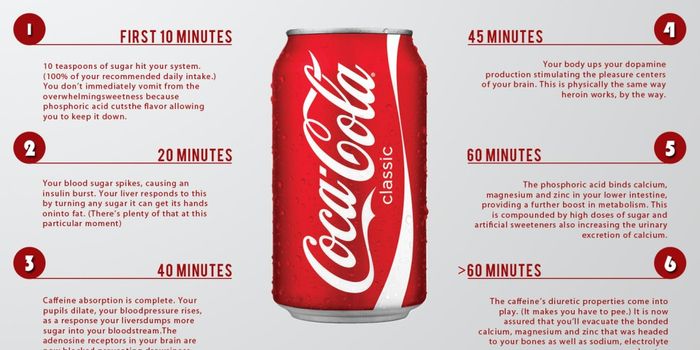

SEP 13, 2017VideosThe average American consumes about 32 teaspoons of sugar daily. This sugar is not the natural kind derived from fruits ...